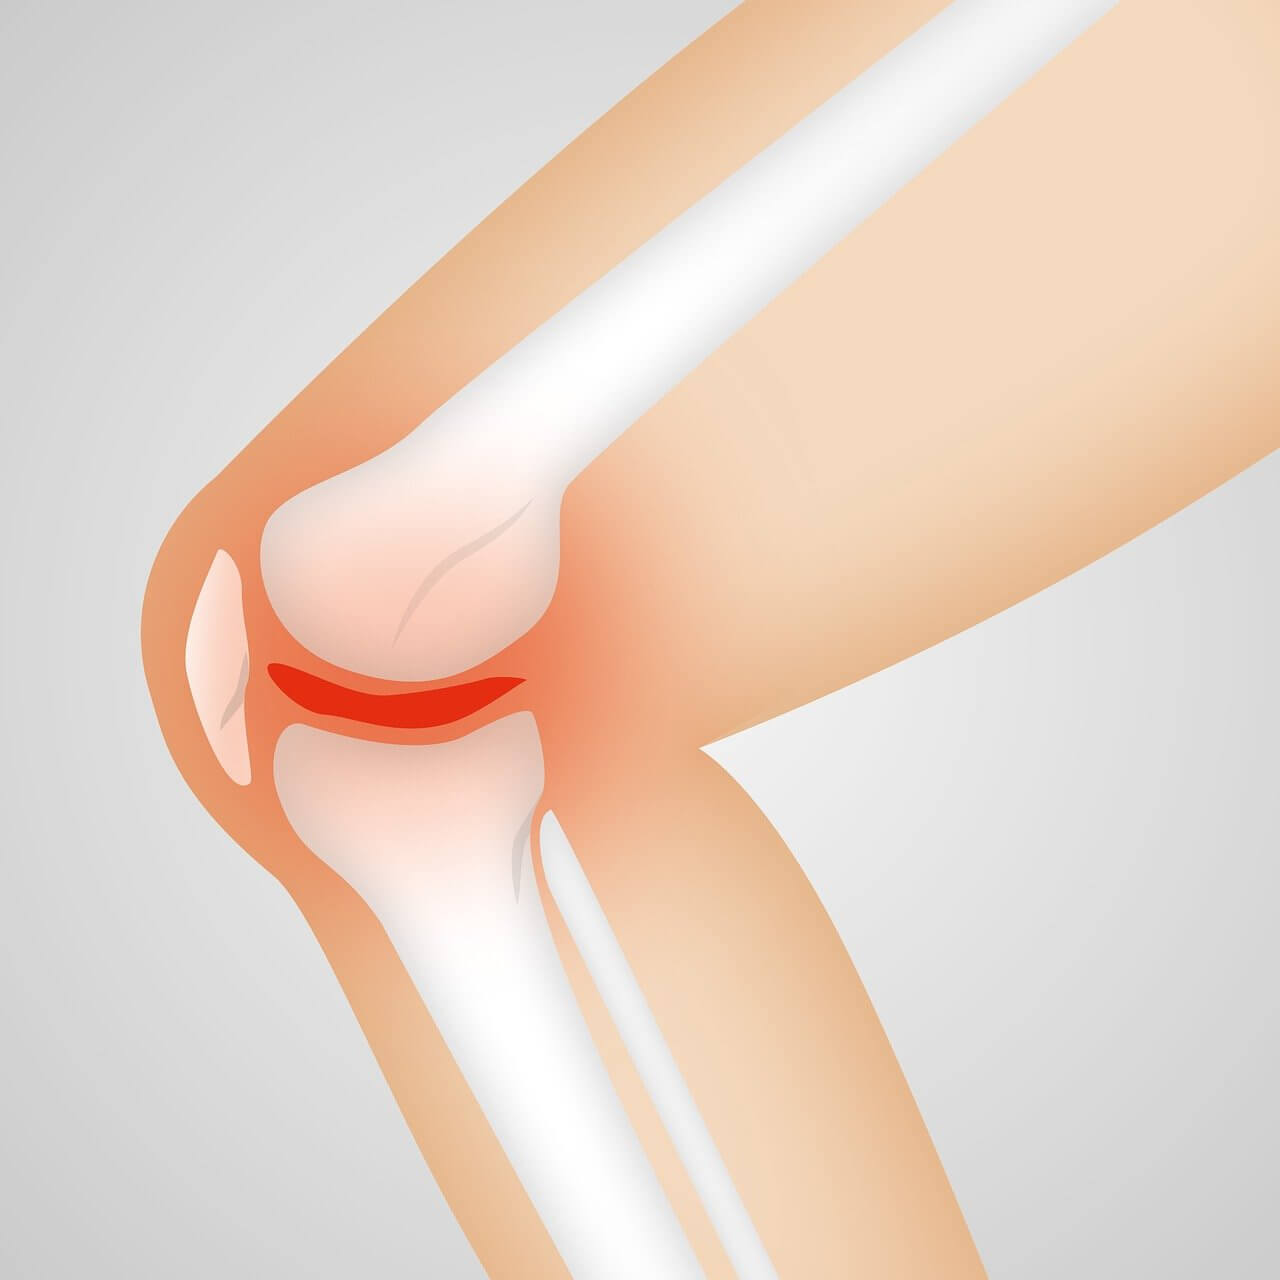

관절염은 관절에 염증이 생기는 질환으로, 주로 통증, 부기, 뻣뻣함 등의 증상을 동반합니다. 관절염은 크게 퇴행성 관절염과 류마티스 관절염으로 나눌 수 있습니다. 퇴행성 관절염은 나이가 들면서 관절의 연골이 닳아 없어지는 현상으로 발생하며, 류마티스 관절염은 면역체계의 이상으로 인해 발생하는 자가면역 질환입니다.

- 부기 : 관절 주위가 붓거나 열감이 느껴질 수 있습니다.

- 관절의 붓기 : 손목, 발목, 무릎 등 여러 관절에서 붓고 열감이 느껴질 수 있습니다.